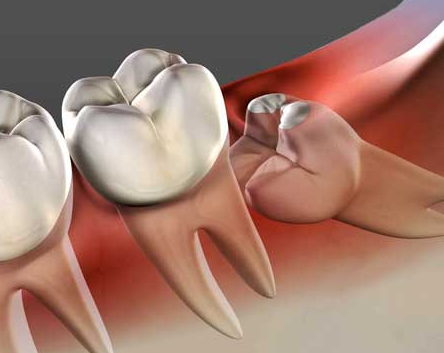

어느 날 갑자기 잇몸 구석이 욱신거리기 시작했다면, 그것은 인류 진화의 흔적이자 치과 의사들의 영원한 숙제인 사랑니가 존재감을 드러낸 신호일 가능성이 큽니다. 사랑니는 예쁘게 나서 제 역할을 하면 좋으련만, 보통은 좁은 잇몸 틈바구니에서 옆 치아를 괴롭히거나 매복되어 염증을 일으키기 일쑤입니다.